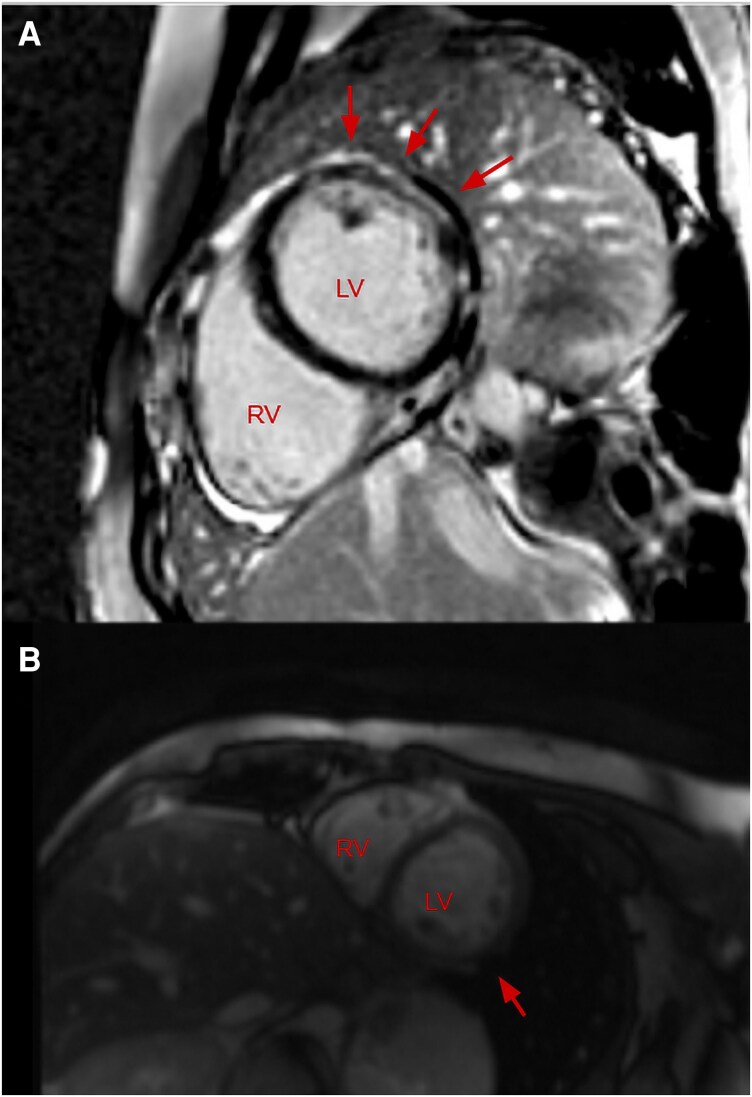

Case summary: A 17-year-old gentleman with a background history of developmental delay, gastrointestinal motility issues, retractile testes, and patellar dislocation presented to our emergency department with chest pain. Investigations revealed static mildly elevated troponin T. An electrocardiogram and transthoracic echocardiogram were both unremarkable. CMR revealed sub-endocardial and mid-wall LGE. He was treated as myocarditis with steroids and colchicine, however symptoms persisted and repeat CMR reported progressive LGE. The diagnosis of myocarditis was reconsidered given an atypical presentation and taking into account his past medical history, and so a whole gene exome was performed. This revealed a dual diagnosis of Klinefelter's Syndrome and a mutation in the dystrophin gene located on the X chromosome.